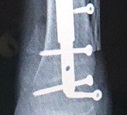

The child, after the diagnosis, was followed at the pediatric oncohaematology department of the Regina Margherita Hospital directed by Professor Franca Fagioli, where she underwent chemotherapy, and in recent days she underwent tumor removal and ankle salvage surgery with donor homoplastic bone reconstruction and synthesis with an extensible nail. The technique performed represents an absolute novelty, in that the nail inserted to stabilize the implant will also allow the regular growth of the limb in the coming years, allowing the lengthening at the end of skeletal maturation. The surgery was planned in detail by two teams of doctors and engineers in the weeks before the surgery. Despite the COVID-19 pandemic, the treatments related to this type of pathologies have been carried out regularly and without delay, even if by institutions of different regions. The child is now well and has just been discharged.

In the last 30 years we have experienced the extraordinary evolution of new surgical techniques specific to the child skeleton, drastically reducing the number of amputations and managing to apply, in most cases, a conservative-reconstructive approach, aimed at improving functional recovery and ensuring a better quality of life for patients and families. The surgical strategies available today are multiple, including virtual bone resection and reconstruction planning, using expandable prosthetic implants, custom-made prostheses (also with 3D printers), homoplastic bone grafts from Musculoskeletal Tissue Banks and vascularized autoplastic bone transplants, original means of synthesis. Different techniques are frequently used in combination with each other with very satisfactory results, but experience on the long term evolution of the implants used is still lacking. Pediatric bone sarcoma surgery, with original therapeutic strategies and constant innovations from the point of view of surgical technique, devices and materials used, is therefore an area on which to deepen research and encourage the presence of a national network of specialized centers to find the most suitable reconstructive solutions for each individual case.